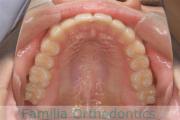

上の前歯の並びが気になるのできれいにしたい、ということで来院されました。マウスピース型矯正装置のひとつ、インビザライン/InvisalignR(薬機法および医薬品副作用被害救済制度の対象外)を用いて治療しました。

非抜歯で2年弱、20回程度の通院で治療が完了しました。

マウスピース矯正は、患者さんの協力に治療結果が左右されるところはリスクと言えるかもしれません。

上顎

下顎